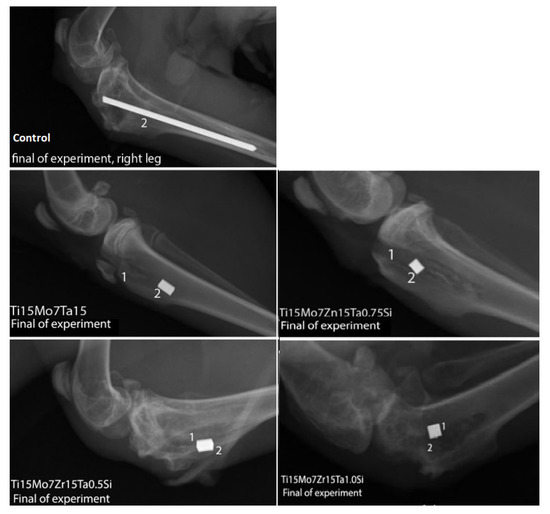

An X-Ray performed in the region of the femur-tibio-patellar joint in latero-lateral incidence identified the presence of implants and in the adjacent peri-implant tissues no abnormal radiological changes were identified, both in the control and in the implanted rabbits (Figure 7).

Figure 7.

X-Ray in control and experimental rabbits, 1, alloy; 2, implantory breach.